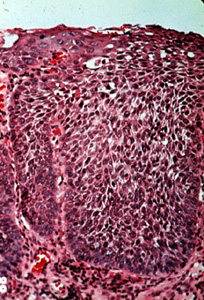

En algunos casos las anormalidades celulares son tan severas y la maduración del epitelio muy pobre, que el espesor entero del epitelio no hay diferencia entre la capa basal y la superficie. Cuando ocurre esto la lesión se designa carcinoma in situ. Todavía no hay infiltración en el tejido conjuntivo.

Con una resolución más alta de la imagen 66, puede ser algo difícil determinar qué lado es la basal y cual es la superficie. Las anormalidades celulares son obvias y la maduración es casi inexistente.

El fracaso de la queratinización del  epitelio, como en este ejemplo típico de carcinoma in situ, significó que la enfermedad sería muy difícil de descubrir clínicamente. Aunque algunos casos son indudablemente invisibles, otros son rojos y ligeramente granulares o aterciopelados  debido a la inflamación y aumento de la vascularidad en el tejido conjuntivo (como es visto aquí), o el carcinoma in situ alterna con focos de displasia de la mucosa que producen queratina. Esto imparte una apariencia roja y blanca manchada a la mucosa que es algo más fácil de descubrir cuando se realiza un examen oral completo.